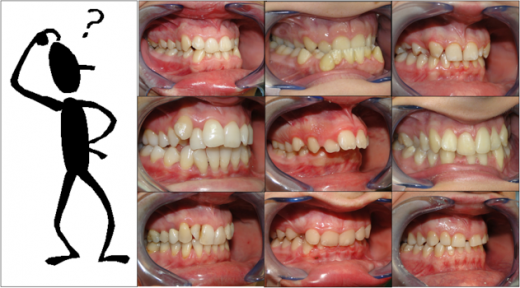

I modelli dentali sono delle riproduzioni di arcate dentali. È possibile distinguere i modelli in: modelli da archivio: fissa un momento clinico irripetibile in senso diagnostico e storico. Tale manufatto accuratamente elaborato entra nella...